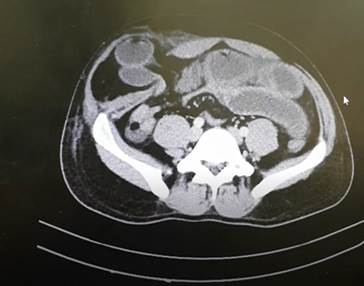

La tomografía computada de abdomen reveló la protrusión de asas delgadas a través de un defecto en la línea de Spiegel. Además, se observa la presencia de un absceso paraherniario (Figura 2). Debido a estos hallazgos, se dispuso el traslado inmediato a quirófano para llevar a cabo la reducción, cierre del defecto herniario y drenaje de la colección.